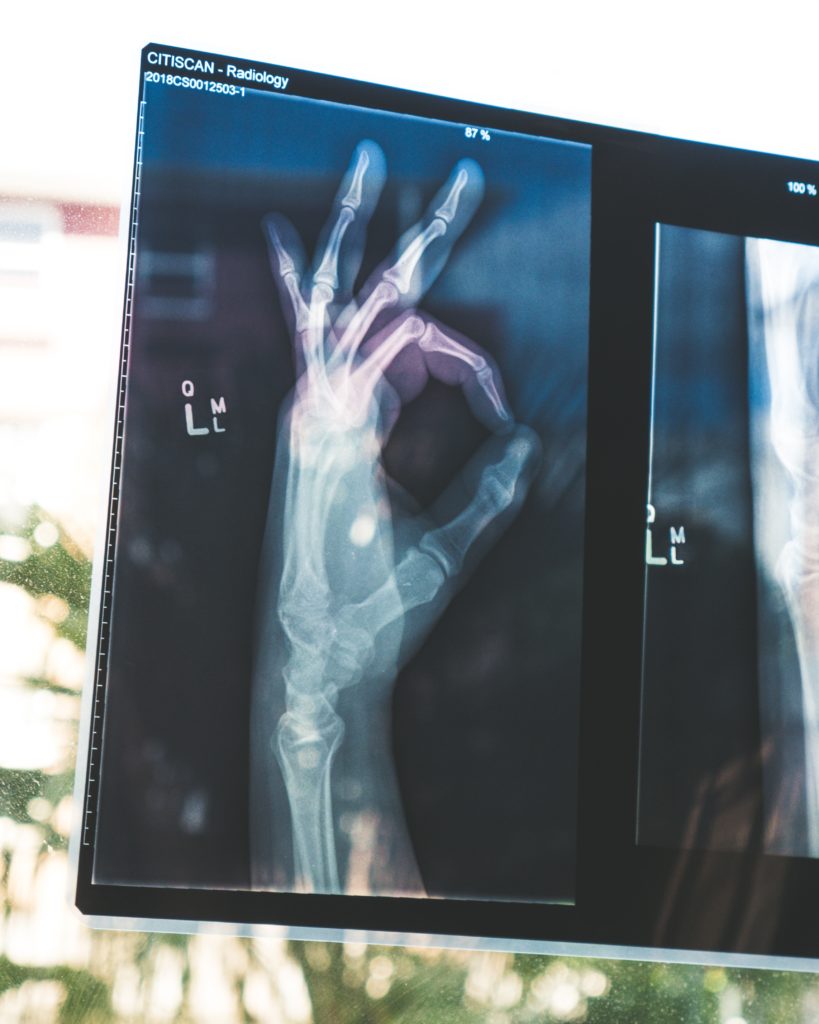

50. Not A Typical X-ray Image

In my whole career as an ER nurse, I've never seen a case like this. One day, a patient came in with abdominal pain. We ran some tests and did an X-ray on his stomach. I went to get the results, and when I saw the X-ray images, my stomach turned upside down. I've never been so disgusted, and I've seen many things! I rushed to find the doctor when my patient was waiting for me, leaned on the door, and said, "Please don't tell my wife." I heard a voice behind me say, "Tell me what exactly?" It was too late. His wife was behind me, and my patient looked like he'd seen a ghost. At the same moment the doctor arrived, and when he saw the X-ray images he almost threw up. The guy has put some kind of bottle inside of him. When his wife asked, "What seems to be the problem?" The doctor calmly replied, "You should talk to your husband." He's going to be in a world of pain after this.

51. Exposed In The Hospital

The doctor EXPOSED my husband's DARK SECRETS! My husband had AWFUL stomach pain. I took him to the ER and I was in full-on panic mode. One moment we were sitting, and the next he was on the floor crying from pain. After a while, the doctor came to tell me the results. "What's going on? How's my husband?" I asked the doctor. He came closer to me with a PALE face and whispered "Your husband is a MONSTER! He's been keeping disgusting secrets from you." I was confused, and he continued "Check his room and you'll find the answer." A few moments later my lawyer came to the hospital. I found out my husband had been inserting some disgusting stuff in him and he's been hiding that from me. When I found out about that, I instantly filed for divorce.